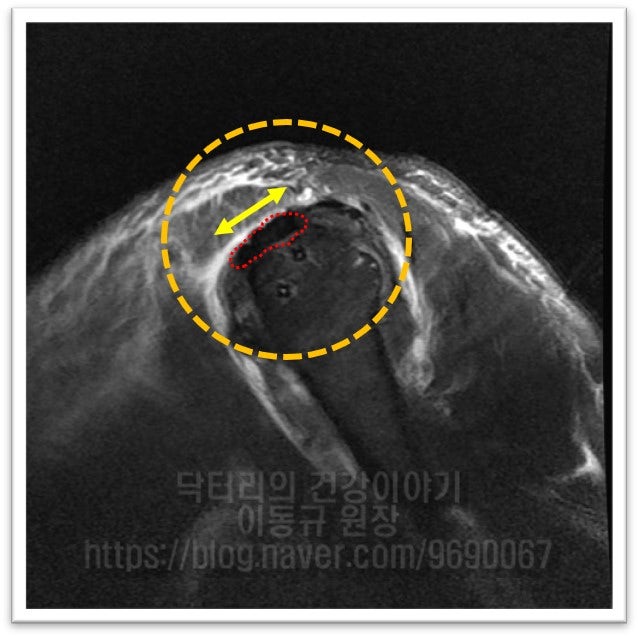

수술 후 MRI 를 비교해 보겠습니다.

이열 봉합법으로 봉합을 하게 되면 1. 보다 많은 파열된 회전근개가 부착될 상완골에 넓은 면적으로 부착될 수 있고. 2. 더 단단히 봉합됨으로써 회전근개에 걸리는 장력을 더 견딜수 있게 되며, 3. 단단히 봉합되었기 때문에 재활을 더 빨리, 편하게 진행할 수 있게 됩니다. 67세의 나이에도 현재 아주 열심히 재활하고 계시고 이제는 밤에도 잘 자고 생활도 잘 하신다고 좋아라 하셨습니다. 개인적으로는 회전근개 파열의 거의 모든 수술에 이열 봉합법을 이용하여 봉합을 합니다. 상기의 이유로 단단히 봉합할 수 있고 초기재활을 빨리 할 수 있기 때문입니다.